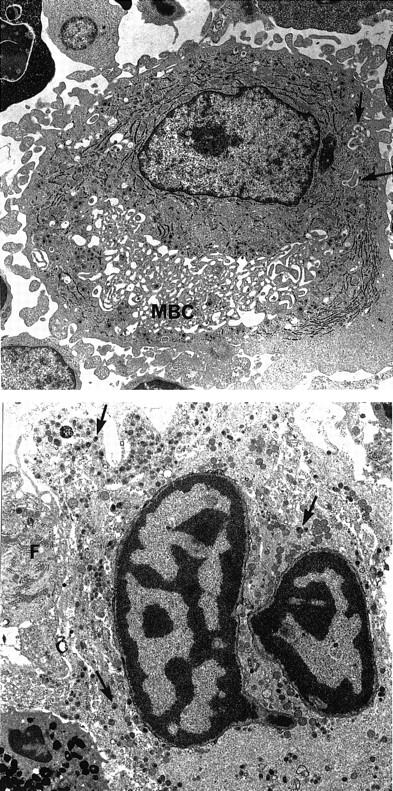

Morphologic examination of peripheral blood smears revealed hypogranular platelets and the presence of some giant platelets (diameter ≥ than that of lymphocytes). Bone marrow aspirates showed normocellular marrow with megakaryocyte hyperplasia. Megakaryocyte morphologic abnormalities included numerous small mononuclear or hyposegmented megakaryocytes, vacuolated cells, and abnormal fragmentation of megakaryocyte cytoplasm into large platelet masses. This abnormal subpopulation coexisted with a population of apparently normal megakaryocytes. Electron microscopic studies showed that alpha granules were produced but appeared to exhibit abnormal cytoplasmic distribution due to the presence of giant membrane complexes with associated smooth endoplasmic reticulum and demarcation membranes (Figure 2). These membrane complexes appeared very early in megakaryocyte maturation and were also observed in cultured megakaryocytes. In addition, numerous large lytic megakaryocytes were seen, some exhibiting apoptotic nuclei (Figure 2). Analysis of platelet membrane proteins showed a markedly reduced amount of GPIb but normal content of GPIIb and GPIIIa. Furthermore, GPIb exhibited a higher apparent molecular weight, suggesting altered glycosylation. Because the ultrastructural features of the patient's megakaryocytes were similar to those described in NF-E2 knockout mice,17 the cDNA and genomic sequence of this gene were analyzed but failed to reveal any mutation. The genomic sequences of GPIb α and β, GPV, and GPIX were also normal.

Ultrastructural aspect of megakaryocytes.

(Top) A large mononucleated megakaryocyte with large membrane complex (MBC). Only few demarcation membranes are free (arrows). Magnification × 4750. (Bottom) Lytic mature megakaryocyte. The nucleus has the typical aspect of apoptotic cells with clumps of chromatin. The cytoplasm contains numerous granules (arrows). The cell membrane and intracytoplasmic membrane are lysed. A granulocytic peroxidase is present at the periphery. Note the presence of a fibroblast (F) closely associated to the lytic megakaryocyte. Magnification × 5320.